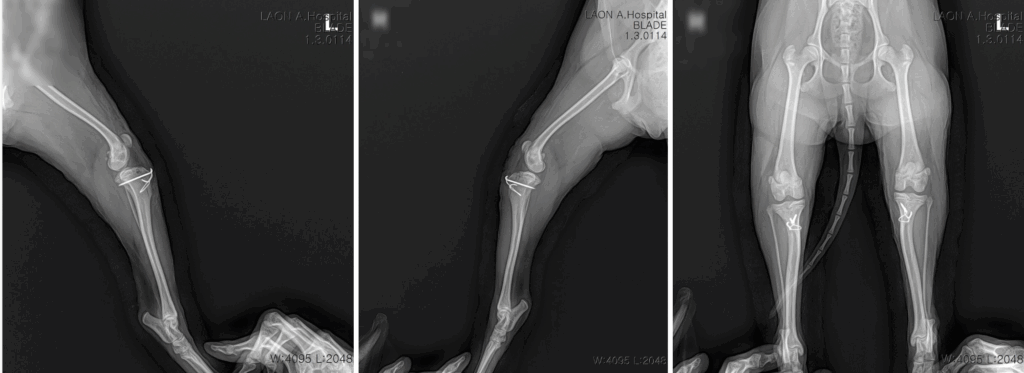

수술 후 방사선 사진 / 출처: 라온동물메디컬센터

수술 직후 입원 치료를 통해 통증 조절과 상처 관리를 시행했고, 보행 회복을 위한 기초 재활 물리치료를 병행하였습니다. 3일째부터는 뒷다리를 디딜 수 있을 정도로 회복되었으며, 퇴원 시에는 보행 시 통증이 크게 줄어든 상태였습니다.